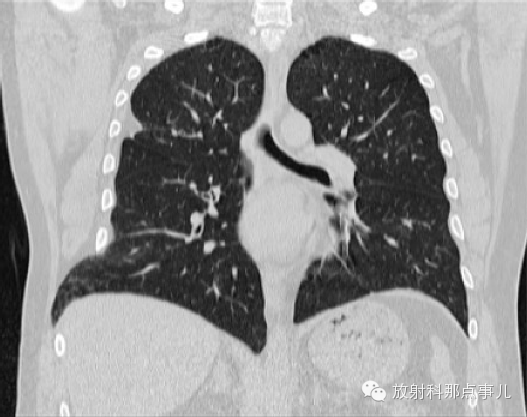

【基本病史】患者咳嗽后出现胸痛症状。

胸部 X 线片显示左肺的基底部肺实质影延伸到胸廓左肋的外侧。胸部 CT 检查结果证明上述结论,左肺实质通过左下肋间外侧疝出,同时左侧胸腔伴有中等量胸腔积液。

胸部CT冠状位